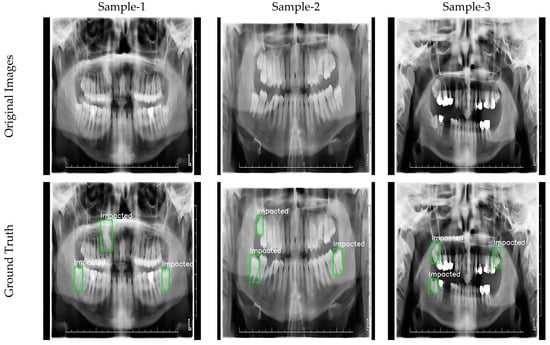

In this study, three different datasets consisting of panoramic radiographs are used for impacted tooth detection. The images in the datasets were carefully selected according to high resolution and quality standards and optimized for training the model. The dataset contains a total of 407 images, 304 images in PNG format with 540 × 380 pixels [44], 53 images in JPG format with 2041 × 1024 pixels [63] and 50 images in PNG format with 3100 × 1300 pixels [64]. This variety was specifically designed to provide results applicable to a larger population of teeth and to evaluate model performance at different resolutions.

Labeling procedures were carefully performed by experts in the field and all images were processed according to the YOLO format. The bounding box method was applied using the Roboflow platform and the positions of the impacted teeth were determined with high accuracy. This detailed labeling process provided a reliable basis for the training and testing phases of the model. Example images of the labeled dataset are shown in Figure 2.

Figure 2.

Sample labeled images.

This dataset has the potential to improve the overall performance of the model by providing samples at a wide range of resolutions for the detection of impacted teeth. The data selection and labeling process ensured a high degree of accuracy in the training and evaluation of the model, while allowing the results of the study to be generalized to a larger population of teeth. The resulting dataset is an important resource for impacted tooth detection studies, both in terms of its size and quality.